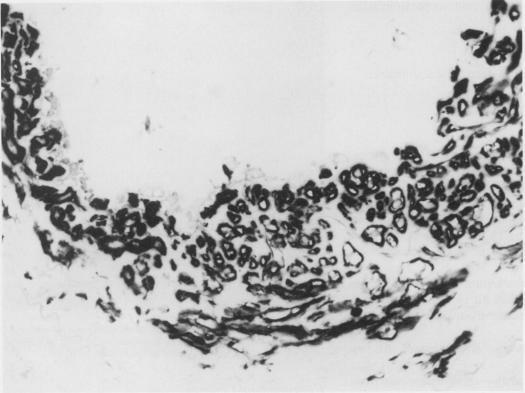

The vascular endothelium plays an important and complex role in vascular allograft rejection. Antigens expressed by the endothelium can act to promote and be the target of rejection reactions, which often lead to thrombosis and ischemic necrosis of the allograft. In this study, segments of femoral artery and femoral vein with or without endothelium were grafted between allogenic or autologous control rats. Immunocompetent Lewis (RT1(1] recipient rats were randomly selected for groups (N = 14 for each) receiving the following: ACI- (RT1a) allografts with intact endothelium, allografts with endothelium removed before operation, autografts with endothelium, and autografts with endothelium removed. Rejection was assessed by graft patency as well as morphologic and ultrastructural changes. At 5 days, the allografts with intact endothelium were totally occluded, whereas allografts without endothelium remained patent, as did autologous control grafts with or without endothelium. Two additional groups (N = 14 each) receiving the de-endothelialized allografts or autografts were examined at 120 days after operation, revealing that grafts in both groups were still patent and had been re-endothelialized. These findings indicate that physical removal of vascular endothelium may depress vessel allograft rejection without immunosuppressive therapy.

血管内皮在血管同种异体移植排斥反应中发挥着重要而复杂的作用。内皮表达的抗原可促进排斥反应并成为其靶标,这常常导致同种异体移植物的血栓形成和缺血性坏死。在本研究中,将有或无内皮的股动脉和股静脉段移植到同种异体或自体对照大鼠之间。随机选择具有免疫活性的Lewis(RT1(1]受体大鼠分为几组(每组N = 14),接受以下移植:具有完整内皮的ACI-(RT1a)同种异体移植物、术前去除内皮的同种异体移植物、具有内皮的自体移植物和去除内皮的自体移植物。通过移植物通畅情况以及形态学和超微结构变化评估排斥反应。在第5天时,具有完整内皮的同种异体移植物完全闭塞,而无内皮的同种异体移植物保持通畅,有或无内皮的自体对照移植物也是如此。另外两组(每组N = 14)接受去内皮同种异体移植物或自体移植物的大鼠在术后120天进行检查,结果显示两组移植物仍保持通畅且已重新内皮化。这些发现表明,在无免疫抑制治疗的情况下,物理去除血管内皮可能会抑制血管同种异体移植排斥反应。